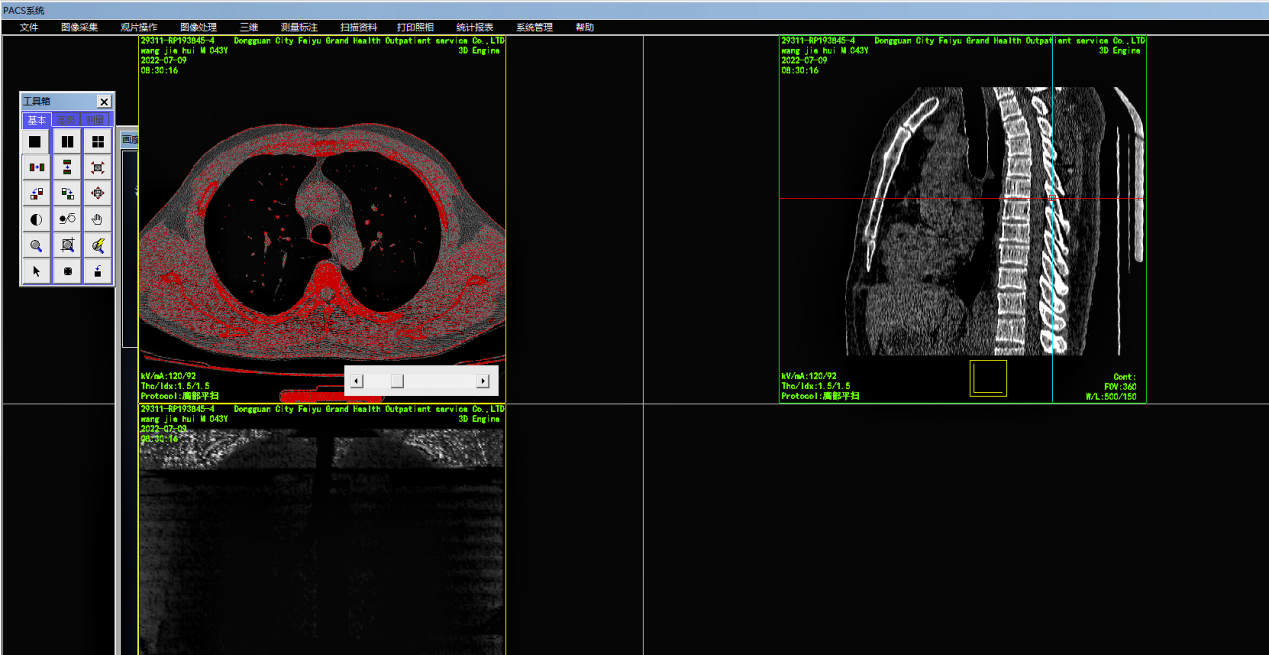

C语言开发的医学影像数字化PACS系统源码 带三维重建和还原的PACS源码

PACS全称Picture Archivingand Communication Systems。它是应用在医院影像科室的系统,主要的任务就是把日常产生的各种医学影像(包括核磁,CT,超声,X光机,红外仪、显微仪等设备产生的图像)通过各种接口(模拟,DICOM,网络)以数字化的方式海量保存起来,当需要的时候在一定的授权下能够很快的调回使用,同时增加一些辅助诊断管理功能。它在各种影像设备间传输数据和组织存储数据具有重要作用。DICOM(DigitalImagingandCommunicationsinMedicine),是医学数字成像和通信的标准。

7、集成三维影像后处理功能。